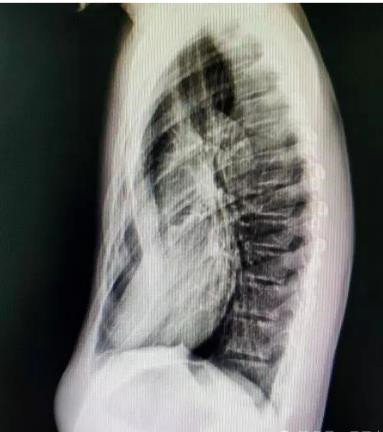

癥狀:胸骨及兩側(cè)肋骨向內(nèi)凹陷,形成 “漏斗狀” 畸形,幼兒期可能癥狀較輕,青春期隨著身高快速增長(zhǎng),凹陷會(huì)逐漸加深,嚴(yán)重時(shí)胸骨可貼近脊柱。

若發(fā)現(xiàn)孩子胸口有凹陷,及時(shí)帶娃到胸外科就診,通過(guò)胸部 X 線、CT 掃描、肺功能測(cè)試、心臟超聲等檢查,明確凹陷程度和心肺受壓情況,避免延誤干預(yù)時(shí)機(jī)。